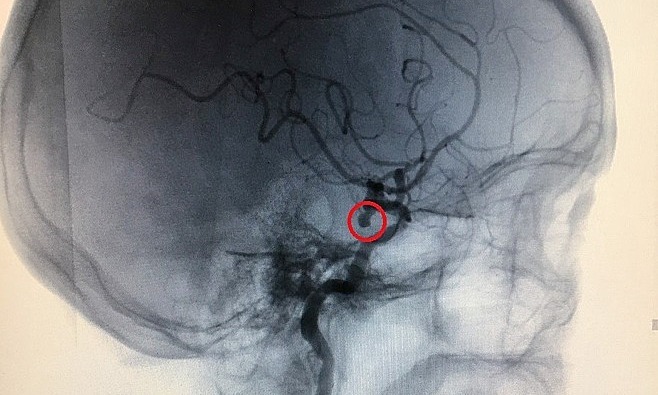

Bác sĩ xác nhận rằng anh ta bị đột quỵ do xuất huyết. Sau khi được cấp cứu, bệnh nhân đã qua cơn nguy kịch, nhưng di chứng để lại là chuột rút, không đi lại được.